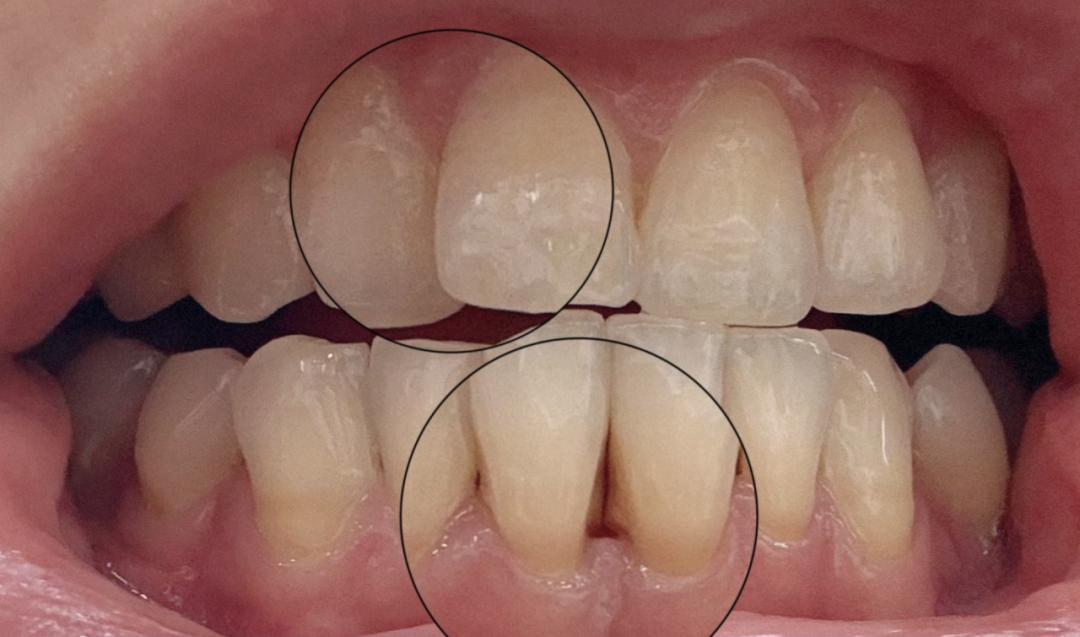

三十歲不到

牙齦已漸漸萎縮、牙縫已變寬的痛,誰懂!!

圖片來源:朋友友情提供